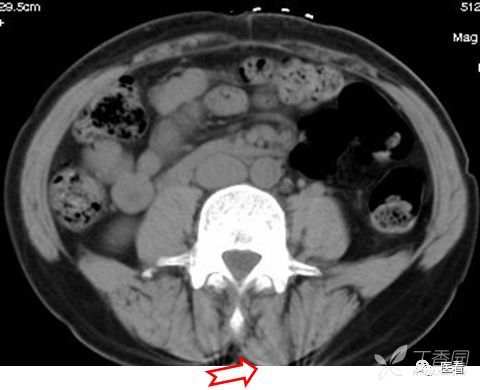

高密度者虽易于辨识,有时亦可能误认为病变。下面这例病例,开始认为是否为软组织异物(白箭)。后来经询问,是从裤袋里掉出的一颗栗子(红箭),可谓无巧不成书。

辨识:1.高密度影直达皮肤表面,边缘平直;2. 边缘环以匀称的低密度带和壳状高密度边缘,与人体组织结构不符;。